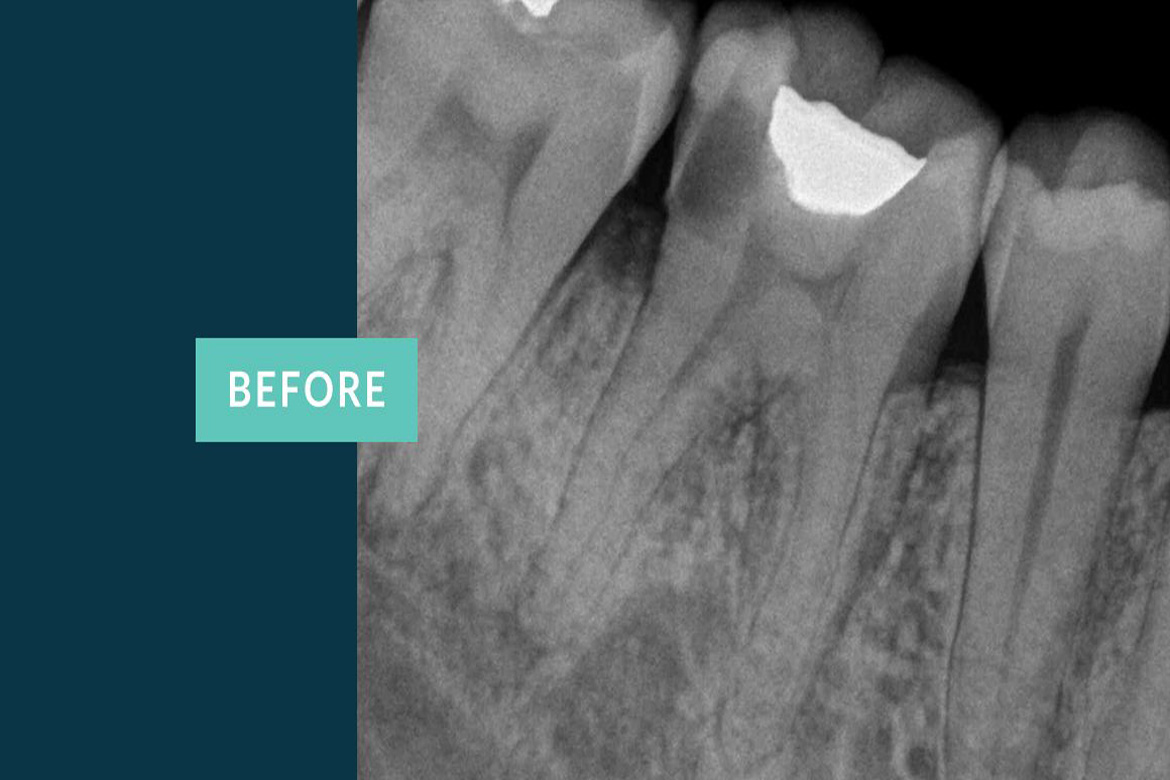

The primary intent of Root canal treatment is to remove the diseased pulp ,clean ,cleanse ,irrigate shape and then fill the canals of the tooth.

Root canal is filled completely with an inert material called Guttaperchathis is to advocate periradicular healing and prevent reinfection of the tooth there by preserving the natural tooth thus maintaining the balance in the oral cavity.